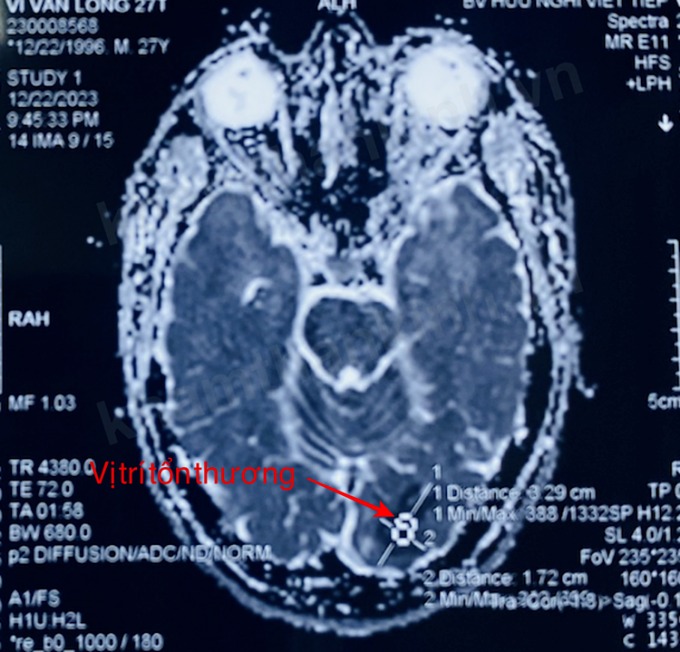

12/01/2024 23:34Chàng trai 27 tuổi đột quỵ sau tắm: Làm gì để tránh đột quỵ trong mùa lạnh?

Ngày 12/1, VnExpress dẫn lời tiến sĩ, bác sĩ Phùng Đức Lâm, Trưởng Khoa Đột quỵ, Bệnh viện Hữu Nghị Việt Tiệp, cho biết bệnh nhân nhập viện khi thị lực mắt phải 8/10, kết quả chụp cộng hưởng từ sọ não cho thấy hình ảnh nhồi máu não.

Các bác sĩ sử dụng phương pháp điều trị thuốc tiêu sợi huyết. Sau ba ngày, mắt người bệnh phục hồi hoàn toàn.

Bác sĩ nhận định trường hợp này với tuổi đời còn rất trẻ cùng những triệu chứng bệnh lý không rõ ràng, rất may mắn đã đến bệnh viện kịp thời, được can thiệp trong giờ vàng, thoát tử vong. Nguyên nhân gây đột quỵ hiện chưa được xác định rõ.